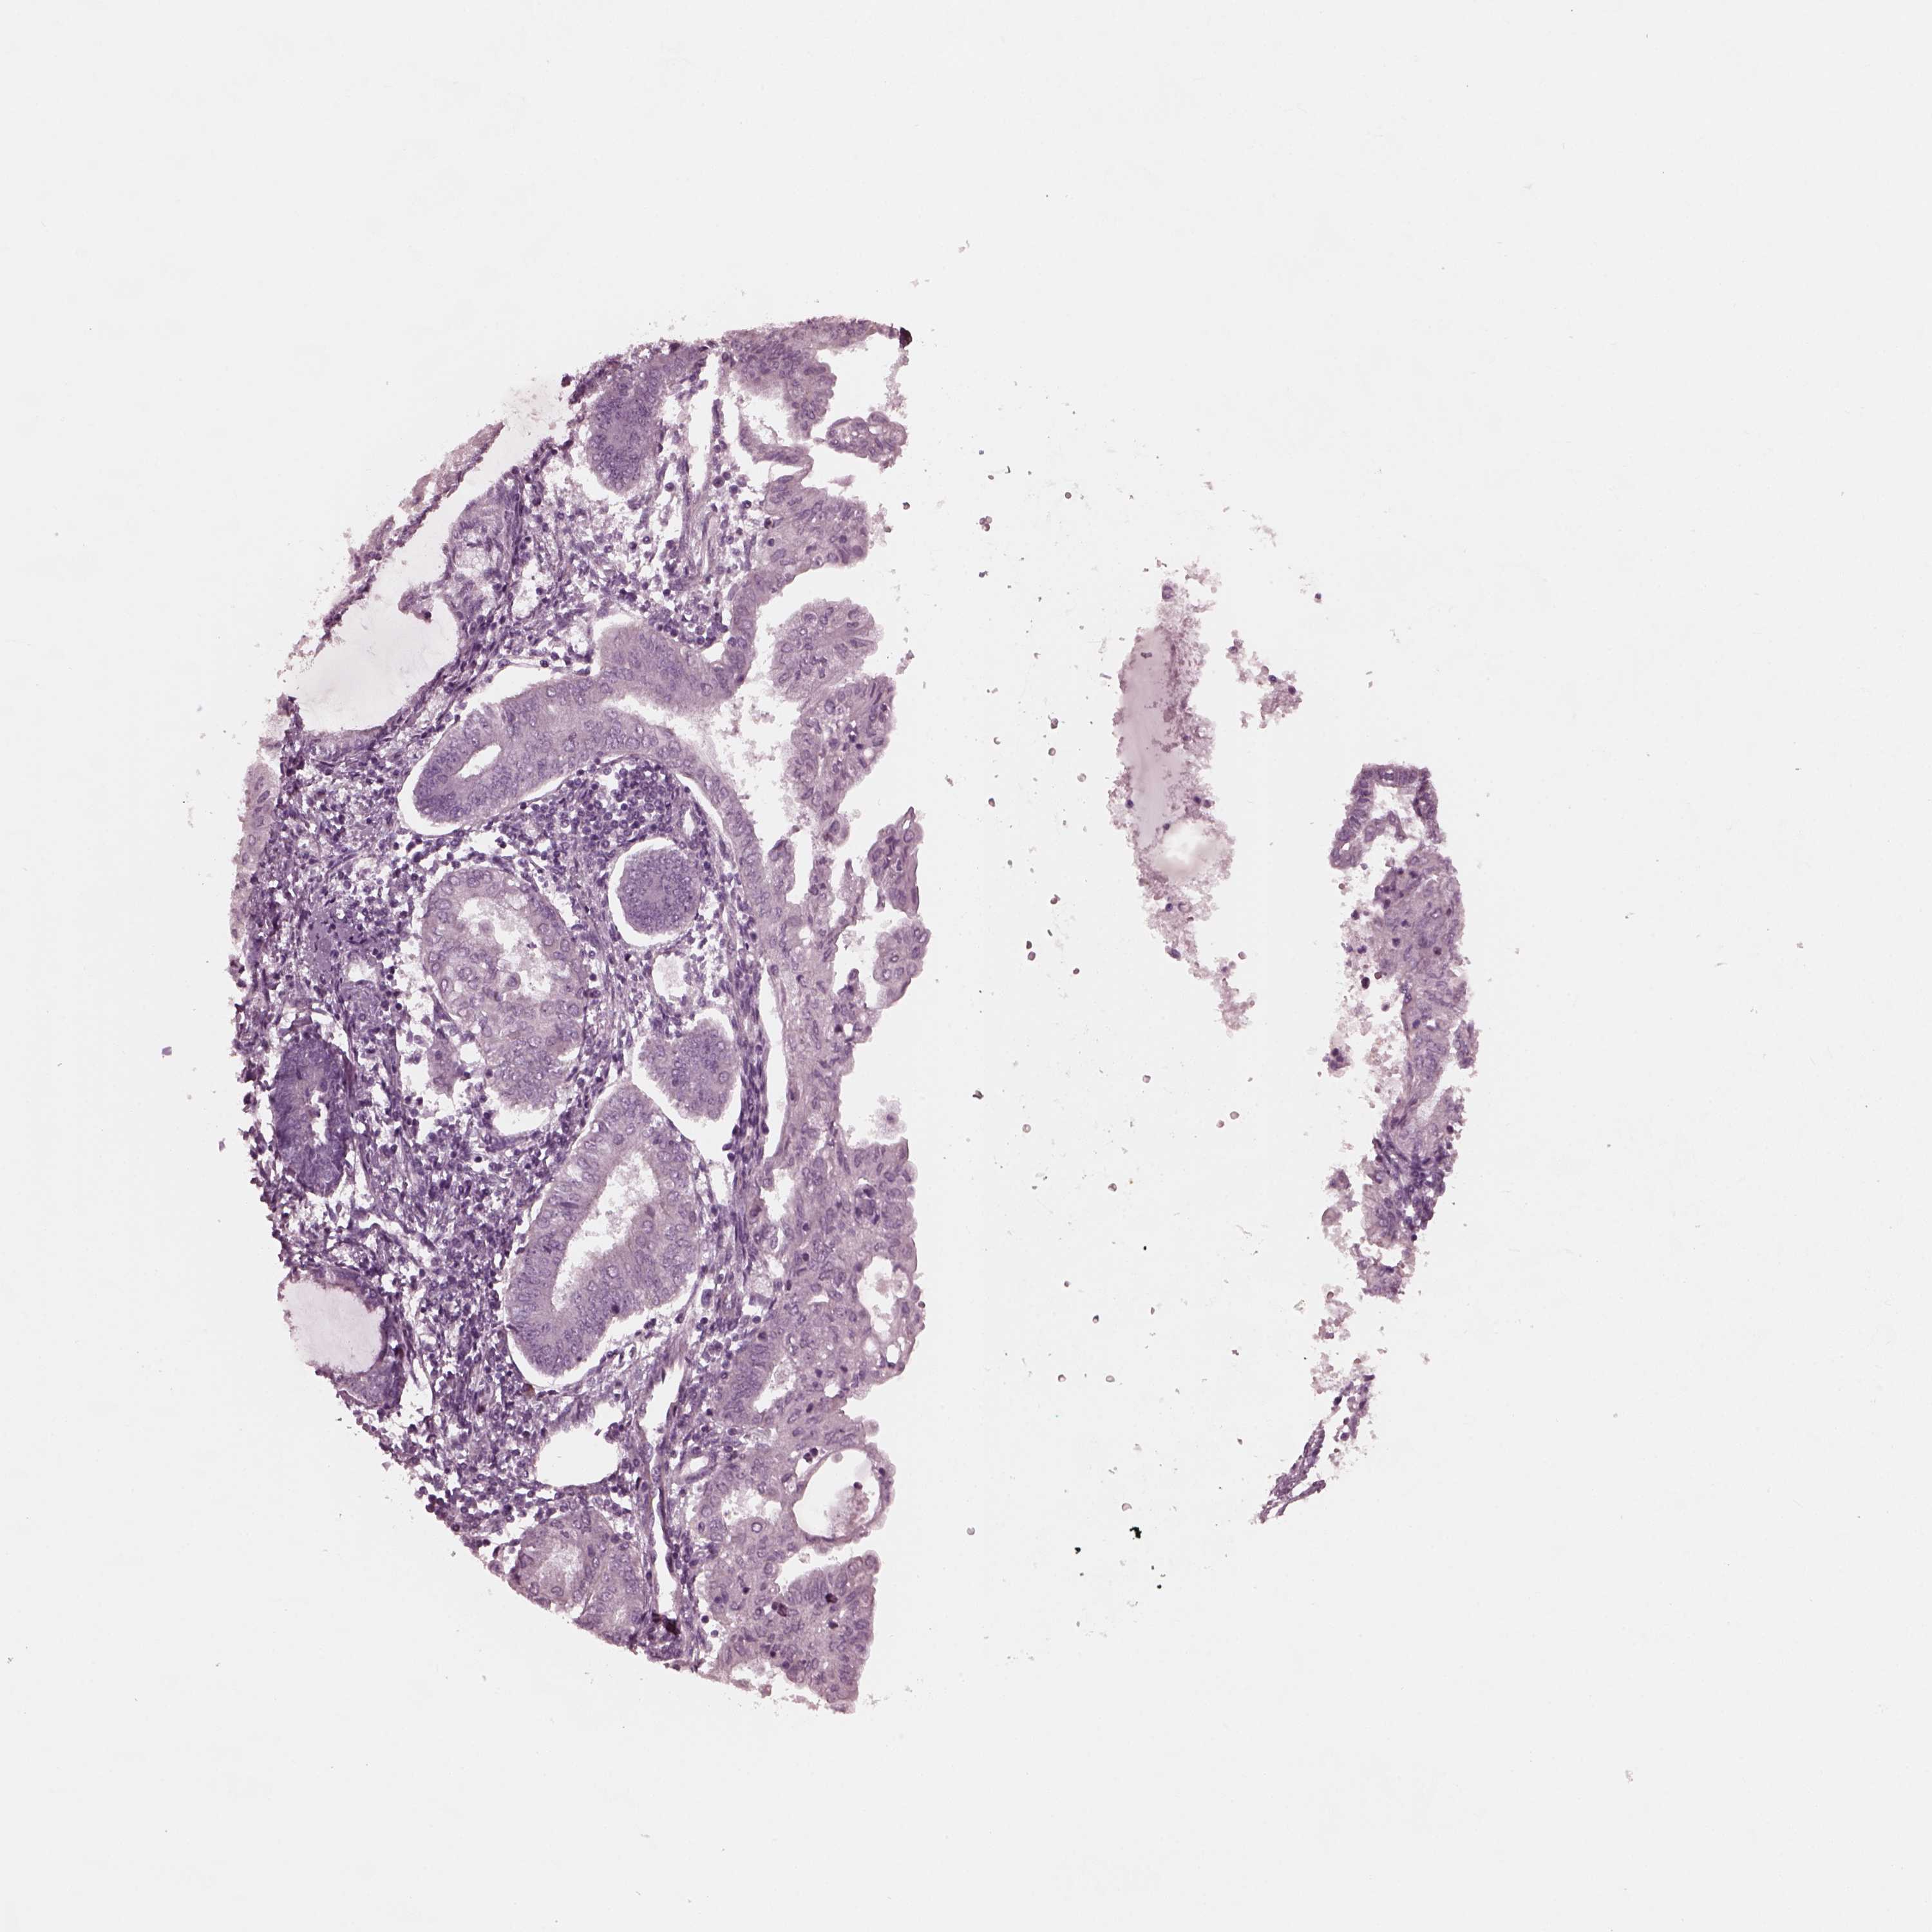

ENDOMETRIAL CANCER - Protein expressioni

A mouse-over function shows sample information and annotation data. Click on an image to view it in a full screen mode. Samples can be filtered based on level of antibody staining by selecting one or several of the following categories: high, medium, low and not detected. The assay and annotation is described here.

Note that samples used for immunohistochemistry by the Human Protein Atlas do not correspond to samples in the TCGA dataset.

Antibody stainingi

Antibody staining in the annotated cell types in the current human tissue is reported as not detected, low, medium, or high, based on conventional immunohistochemistry profiling in selected tissues. This score is based on the combination of the staining intensity and fraction of stained cells.

Each image is clickable and will lead to virtual microscopy that enables deeper exploration of all samples and also displays staining intensity scores, fraction scores and subcellular localization as well as patient and tissue information for each sample.

Antibody HPA038811

Staining

High

Medium

Low

Not detected

Intensity

Strong

Moderate

Weak

Negative

Quantity

>75%

75%-25%

<25%

None

Location

Nuclear

Cytoplasmic/membranous

Cytoplasmic/membranous,nuclear

Adenocarcinoma, NOS

Adenocarcinoma, metastatic, NOS